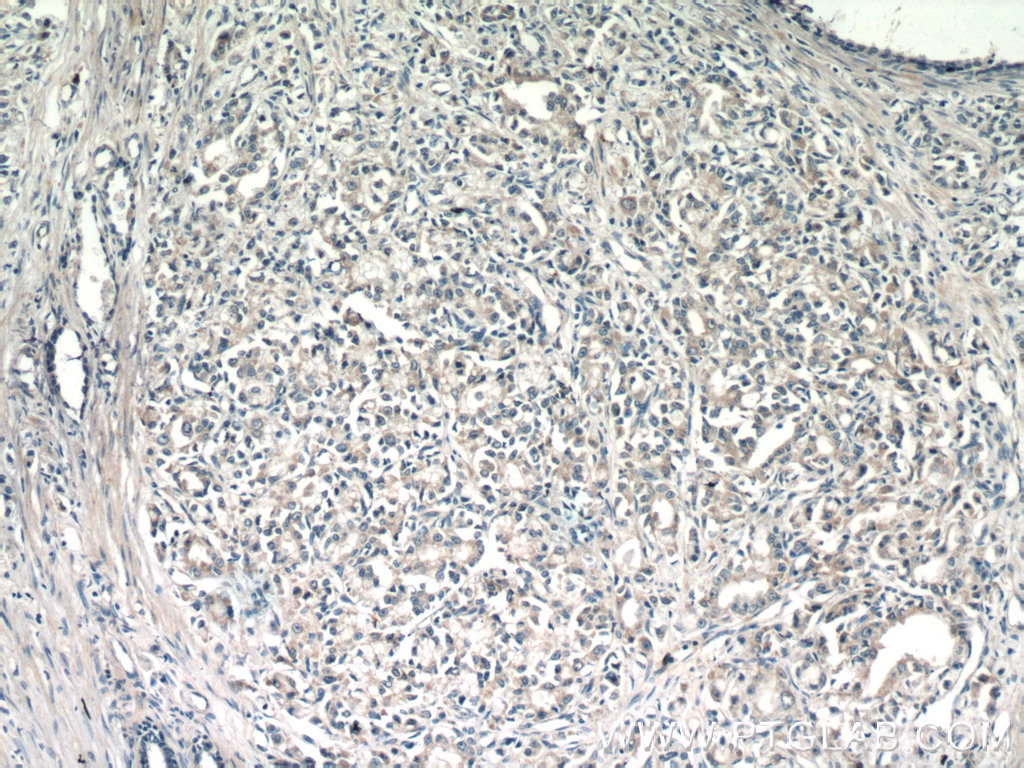

TMEM71 抗体

产品名称: TMEM71 抗体

英文名称: TMEM71 Antibody

产品编号: XY16722-1-

使用范围: WB,ELISA,IHC-P,IHC-F,IF